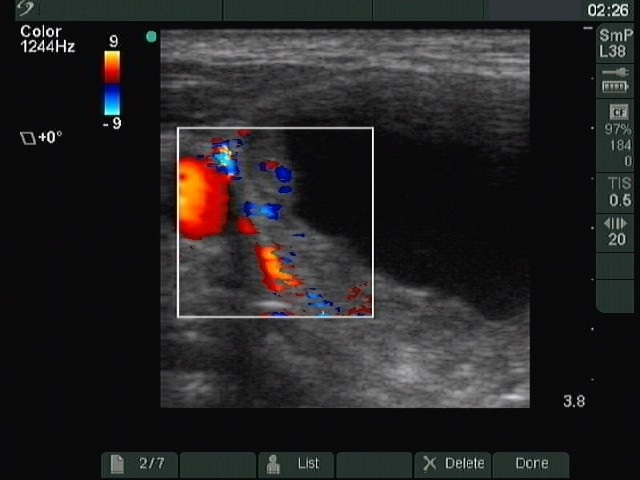

Ultrasonography : the thyroids were echonormal. There was a cystic nodule with an echonormal solid part in the right lobe.

Five sessions of sclerotherapy were performed. We gave 19.8 mL alcohol during five sessions of ethanol sclerotherapy. We demonstrate the first and the third sessions.